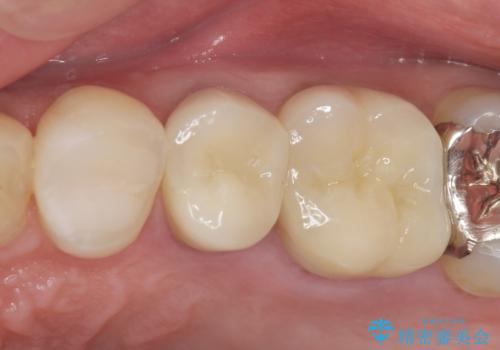

セラミックインレーと根管治療を伴うセラミッククラウン